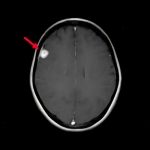

断層撮影

手術前1